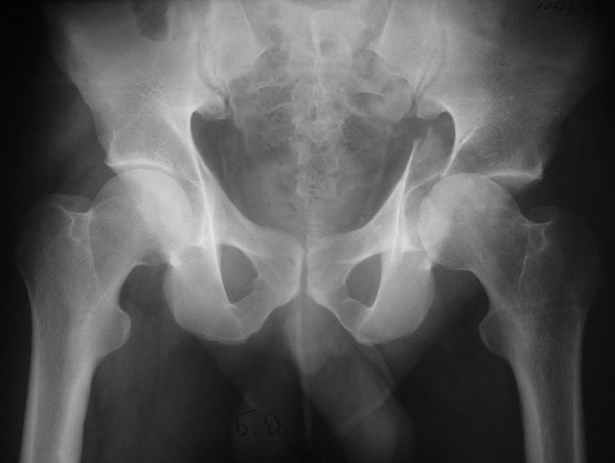

Уважаемые коллеги,Мужчина 36 лет от роду попал в ДТП 24.08.04 Рентгенограммы в приложении.

Диагноз- перелом с вовлечением таза, разрыв правого сакро-илиак сочленения vertical shear injury, перелом крыла подвздошной кости?, перелом ацетабулум Т type или Both column?, перелом шейки бедра, перелом проксимального отдела бедра.

перелом крыла правой подвздошной кости, перелом обеих колонн вертлужной впадины, двусторонний перелом лонных костей (С2.2) повреждение передних связок правого крестцово-подвздошного сочленения,

ипсилатеральный перелом шейки и диафиза бедра.